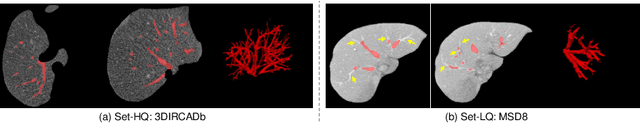

Abstract:Manually segmenting the hepatic vessels from Computer Tomography (CT) is far more expertise-demanding and laborious than other structures due to the low-contrast and complex morphology of vessels, resulting in the extreme lack of high-quality labeled data. Without sufficient high-quality annotations, the usual data-driven learning-based approaches struggle with deficient training. On the other hand, directly introducing additional data with low-quality annotations may confuse the network, leading to undesirable performance degradation. To address this issue, we propose a novel mean-teacher-assisted confident learning framework to robustly exploit the noisy labeled data for the challenging hepatic vessel segmentation task. Specifically, with the adapted confident learning assisted by a third party, i.e., the weight-averaged teacher model, the noisy labels in the additional low-quality dataset can be transformed from "encumbrance" to "treasure" via progressive pixel-wise soft-correction, thus providing productive guidance. Extensive experiments using two public datasets demonstrate the superiority of the proposed framework as well as the effectiveness of each component.